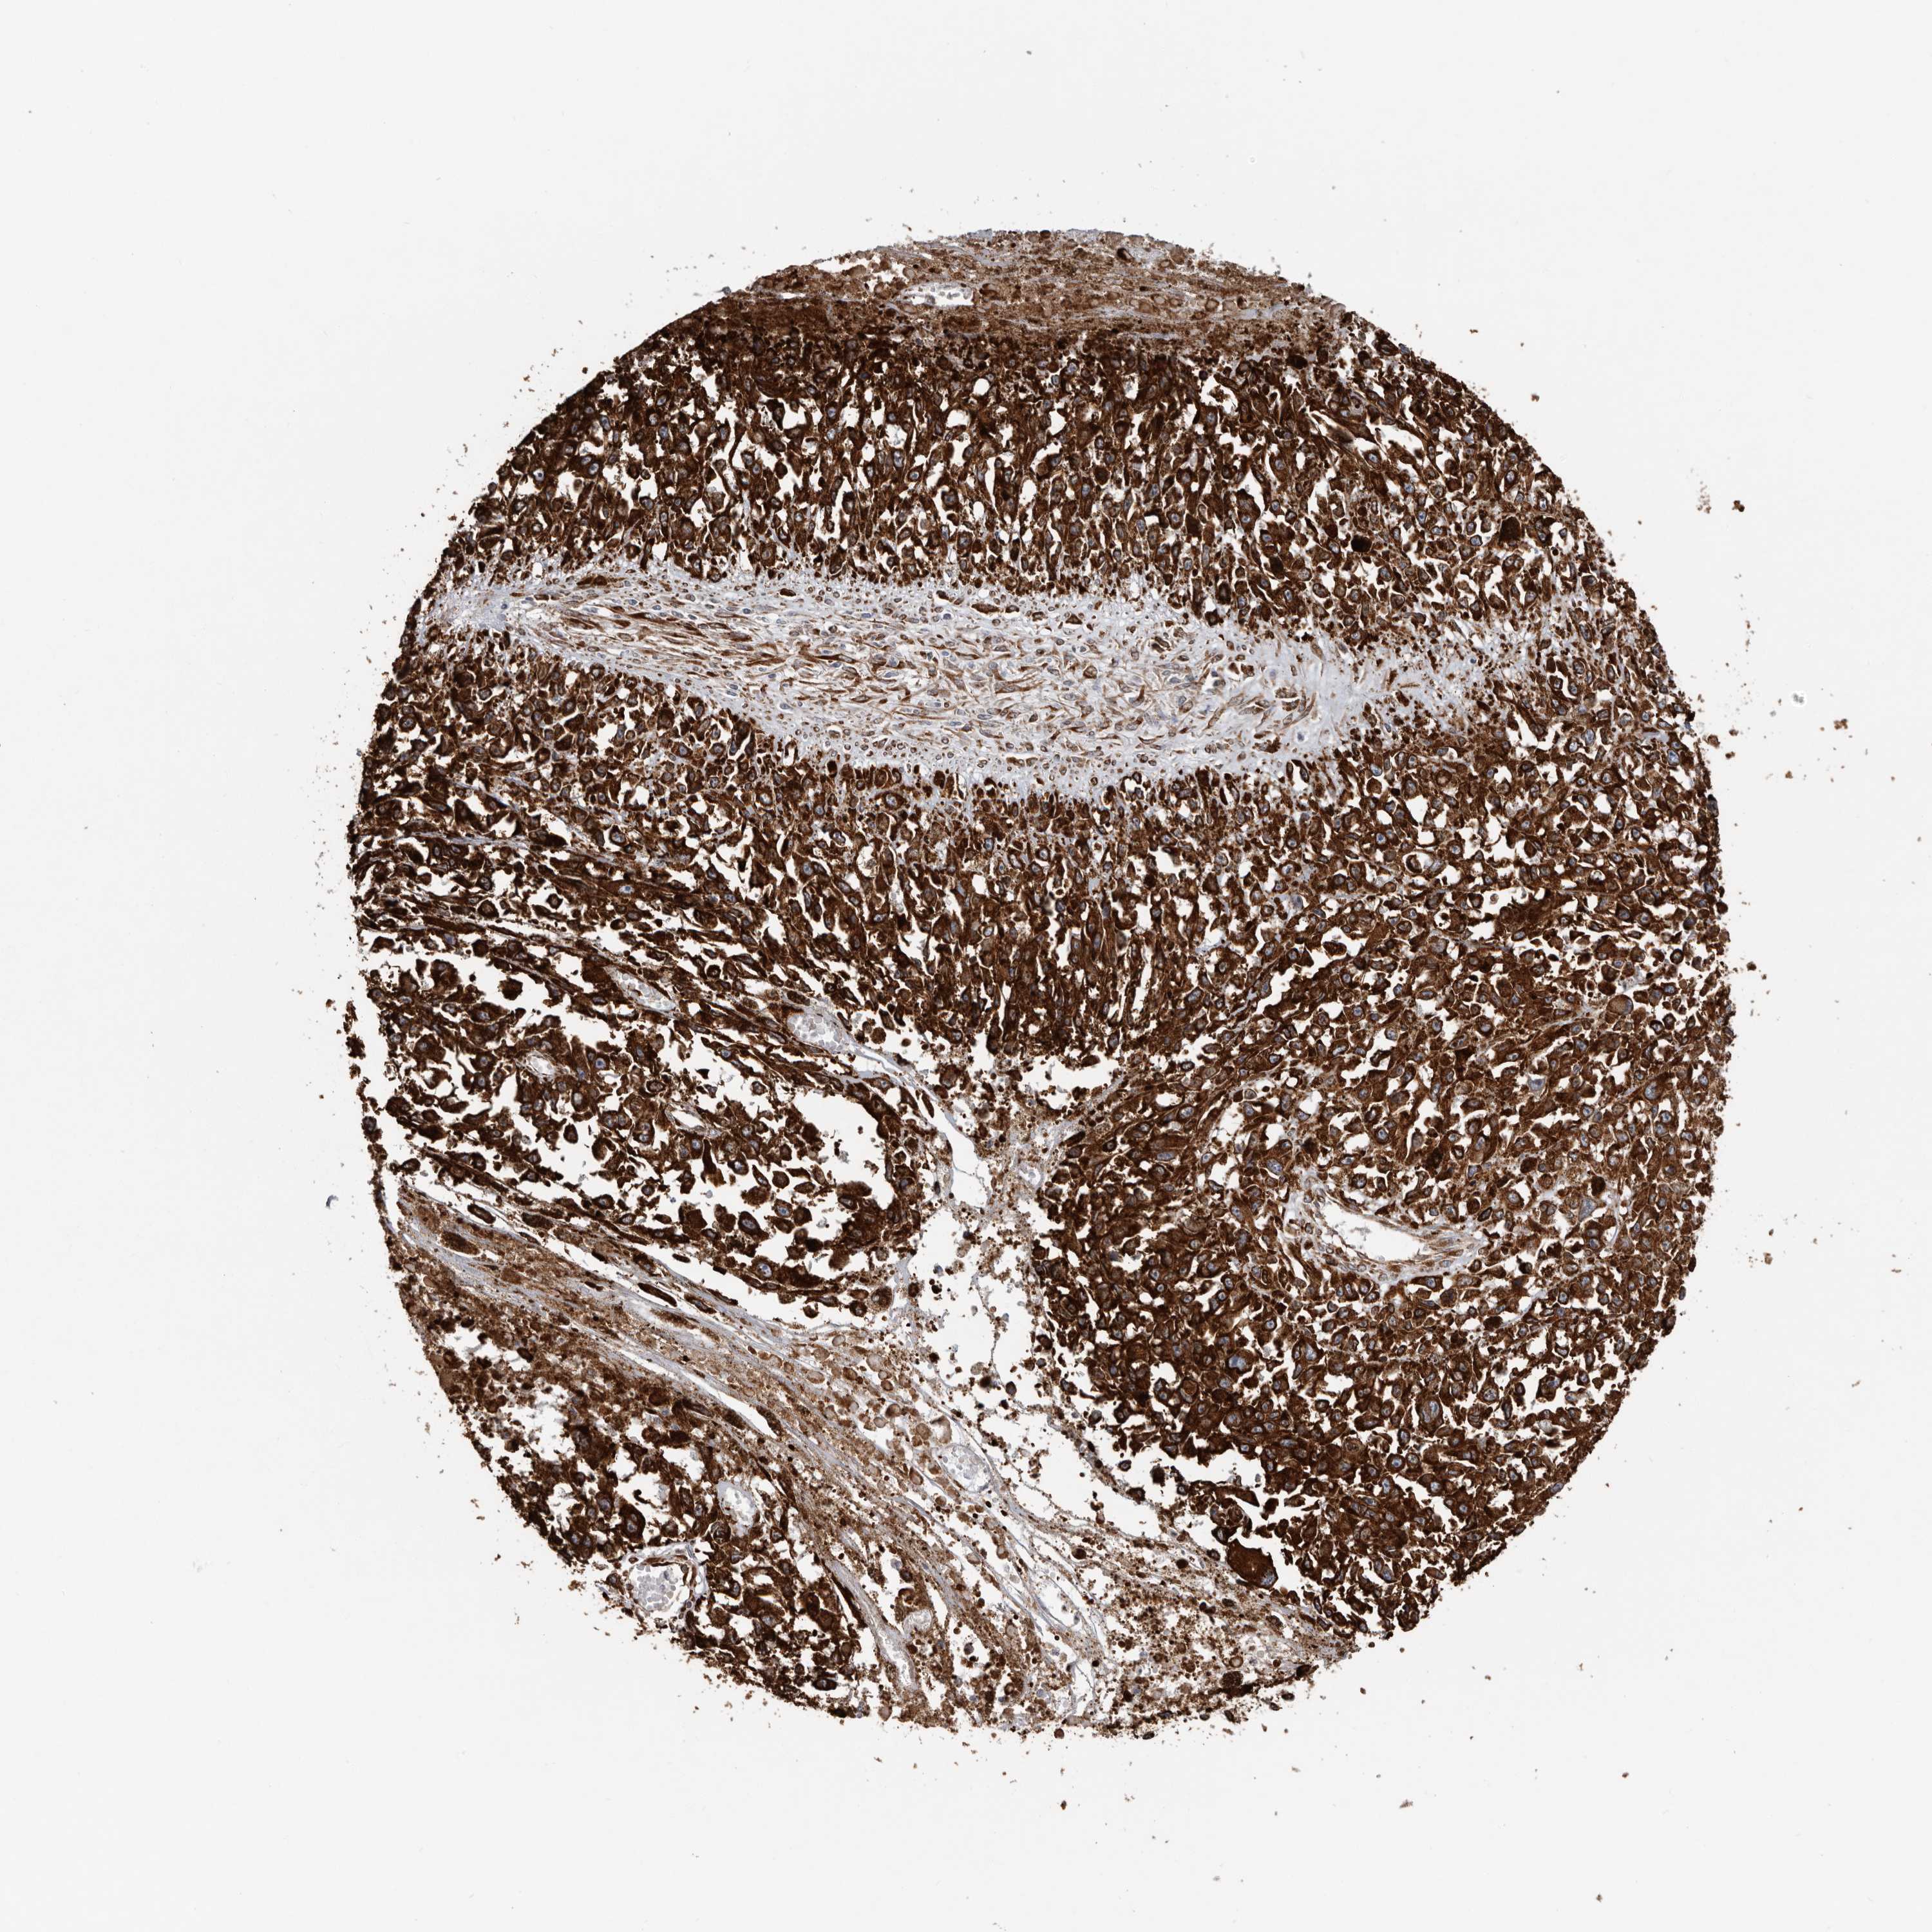

MELANOMA - Protein expressioni

A mouse-over function shows sample information and annotation data. Click on an image to view it in a full screen mode. Samples can be filtered based on level of antibody staining by selecting one or several of the following categories: high, medium, low and not detected. The assay and annotation is described here.

Note that samples used for immunohistochemistry by the Human Protein Atlas do not correspond to samples in the TCGA dataset.

Antibody stainingi

Antibody staining in the annotated cell types in the current human tissue is reported as not detected, low, medium, or high, based on conventional immunohistochemistry profiling in selected tissues. This score is based on the combination of the staining intensity and fraction of stained cells.

Each image is clickable and will lead to virtual microscopy that enables deeper exploration of all samples and also displays staining intensity scores, fraction scores and subcellular localization as well as patient and tissue information for each sample.

Antibody HPA028355

Antibody HPA028357

Staining

High

Medium

Low

Not detected

Intensity

Strong

Moderate

Weak

Negative

Quantity

>75%

75%-25%

<25%

None

Location

Nuclear

Cytoplasmic/membranous

Cytoplasmic/membranous,nuclear

Malignant melanoma, NOS

Malignant melanoma, Metastatic site